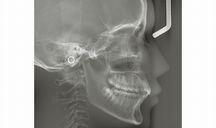

小児歯科歯科歯科口腔外科矯正歯科

・日本矯正歯科学会 認定医